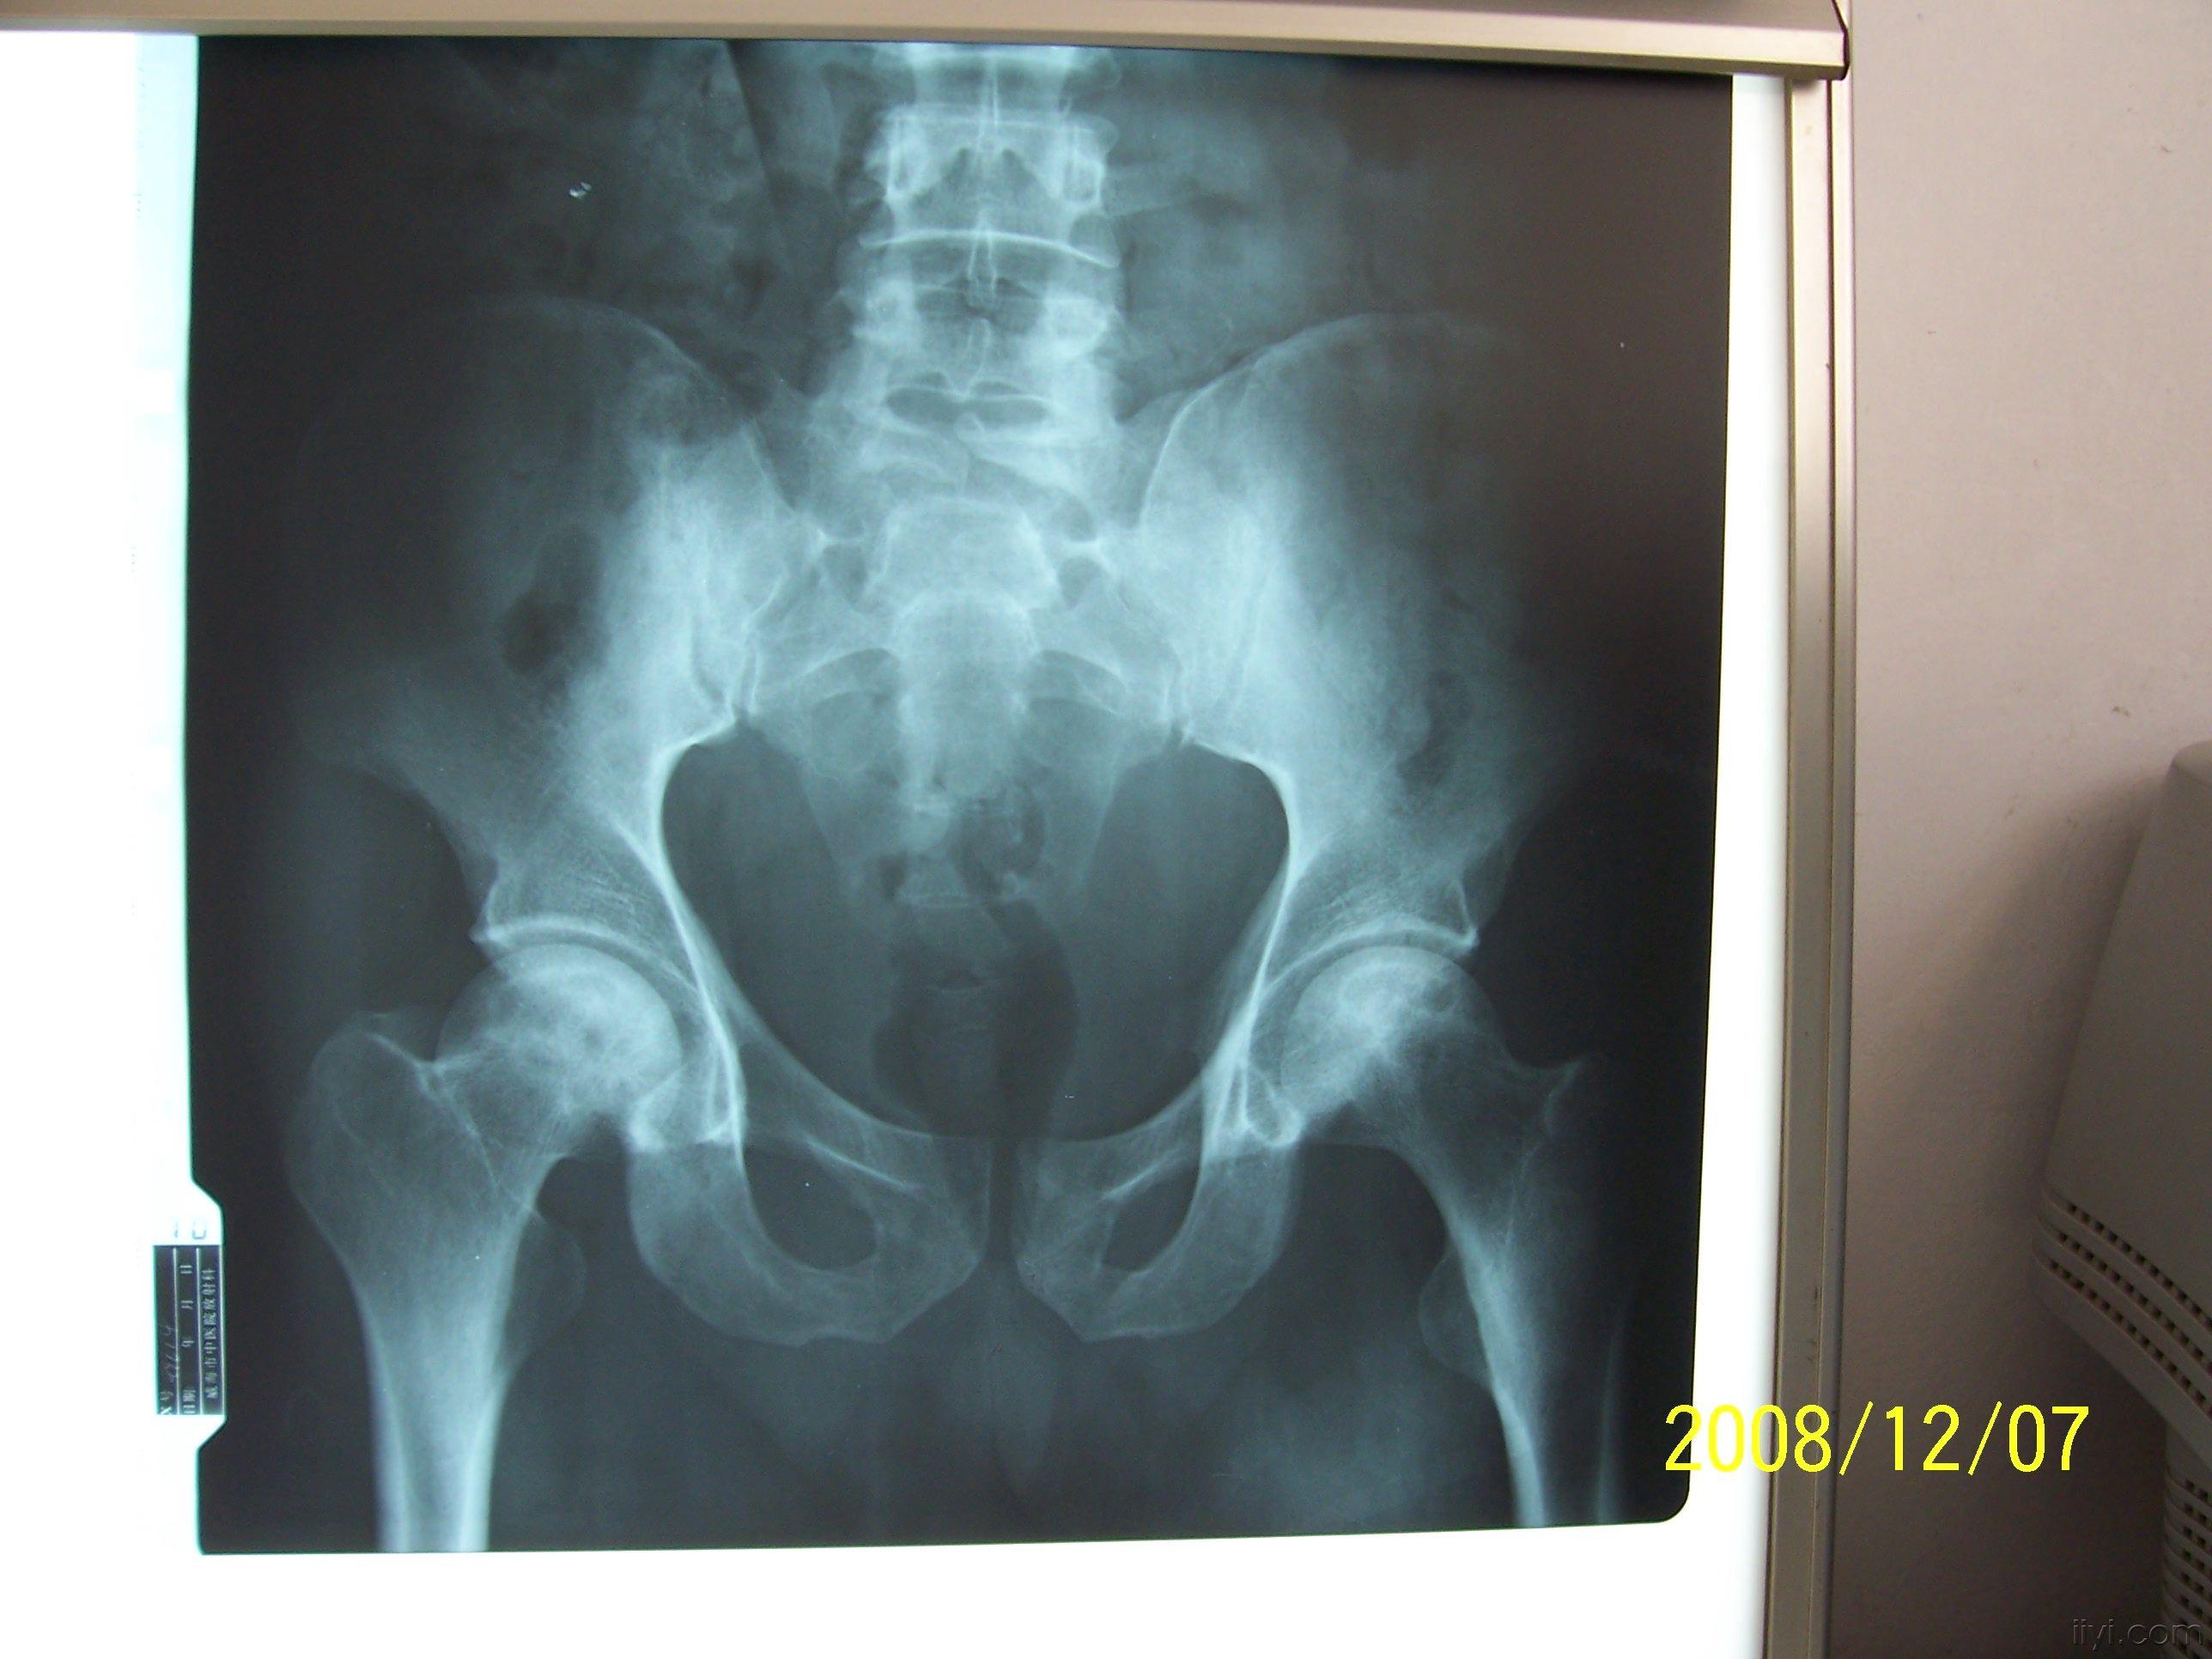

骨梗死影像表现

图片尺寸960x720

骨梗死?